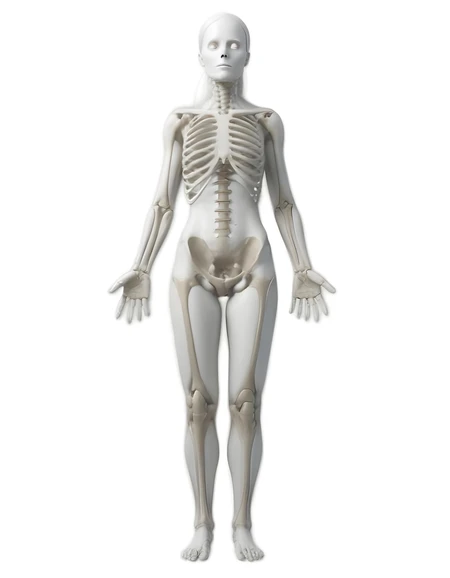

white woman skeleton

32 Photos